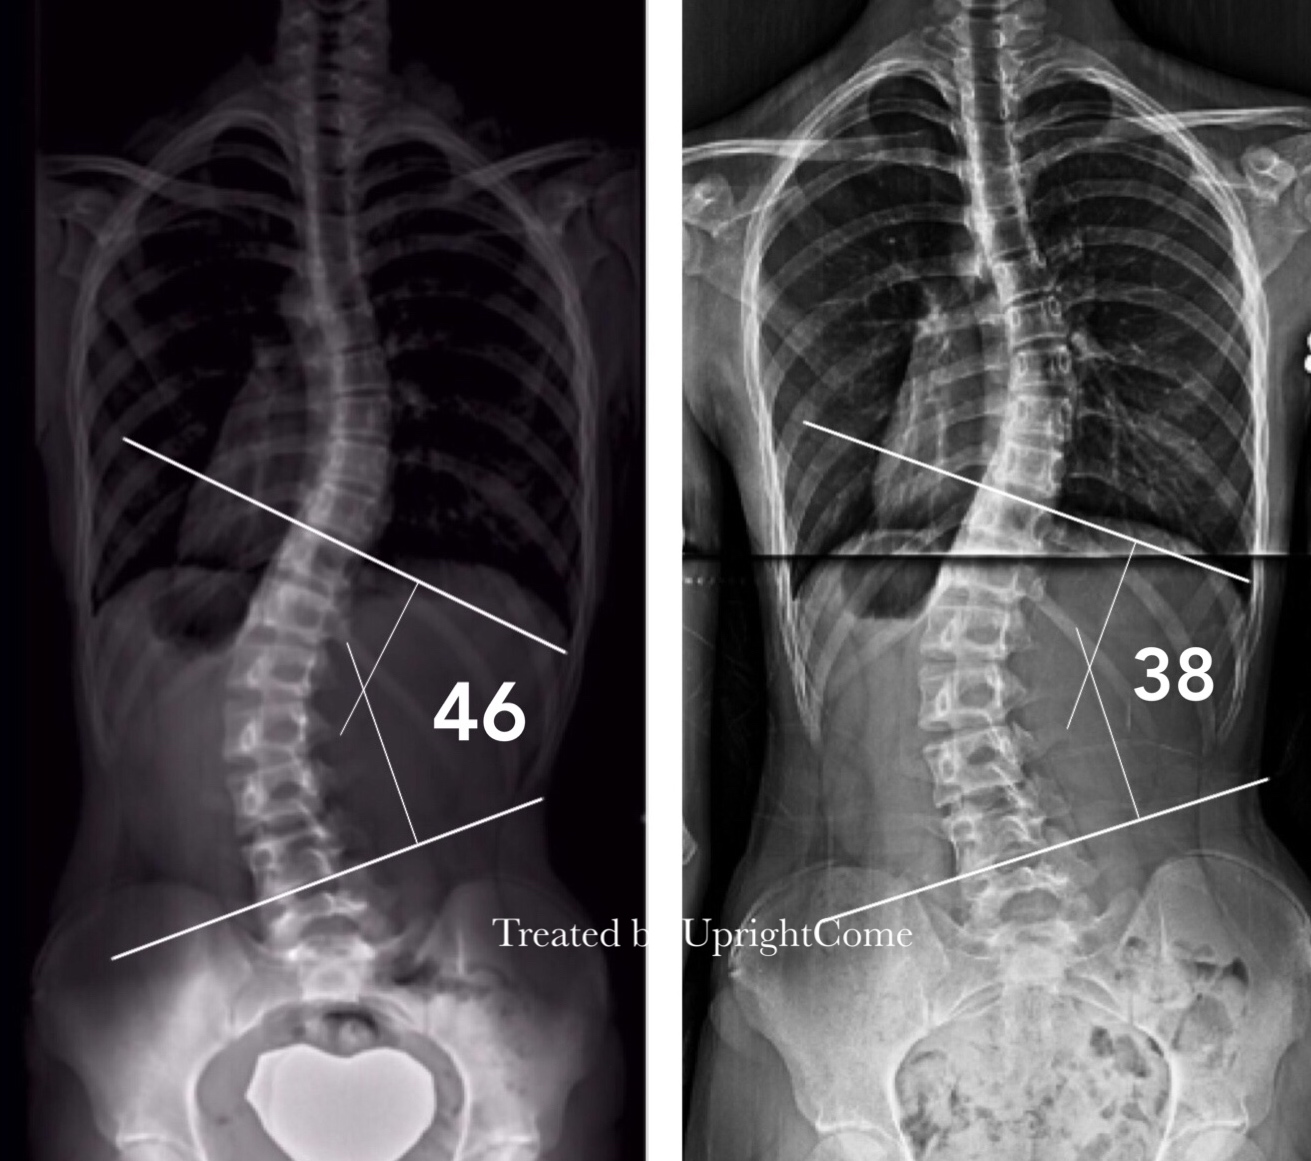

Case 10, 15 years old, 46° Cobb

![脊椎側彎患者經過側彎矯正治療後,腰椎角度由46度減少到38度。]()